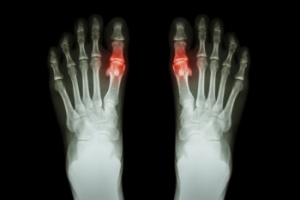

Gout Pain Can Be Managed

Gout is a painful, inflammatory form of arthritis. Those affected will typically feel an intense stiffness in the joints of their feet, particularly in the big toe. Schedule a visit to learn about how gout can be managed and treated.

Buildup of Tophi in Gout

What Is Gout?

Gout is a form of arthritis that is characterized by sudden, severe attacks of pain, redness, and tenderness in the joints. The condition usually affects the joint at the base of the big toe. A gout attack can occur at any random time, such as the middle of the night while you are asleep.

Symptoms

• Intense Joint Pain - Usually around the large joint of your big toe, and it most severe within the first four to twelve hours

• Lingering Discomfort - Joint discomfort may last from a few days to a few weeks

• Inflammation and Redness -Affected joints may become swollen, tender, warm and red

• Limited Range of Motion - May experience a decrease in joint mobility

Gout

Gout is a form of arthritis that is caused by a buildup of uric acid crystals in the joints. This considered to be one of the most frequently recorded medical illnesses throughout history. Gout occurrences in the US have risen within the past twenty years and the condition now affects 8.3 million people which is 4% of all Americans. Researchers have found that gout affects men more than women and African-American men more than white men.

Symptoms of gout are warmth, swelling, discoloration, and tenderness in the affected joint area. The small joint on the big toe is the most common place for a gout attack to occur.

Diagnosis for gout is done by checking the level of uric acid in the joints and blood. Your podiatrist may also prescribe medicine to reduce uric acid buildup in the blood, which will help prevent any gout attacks.